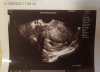

GratulacjeTez sie pochwale w 7t+5 [emoji3059]